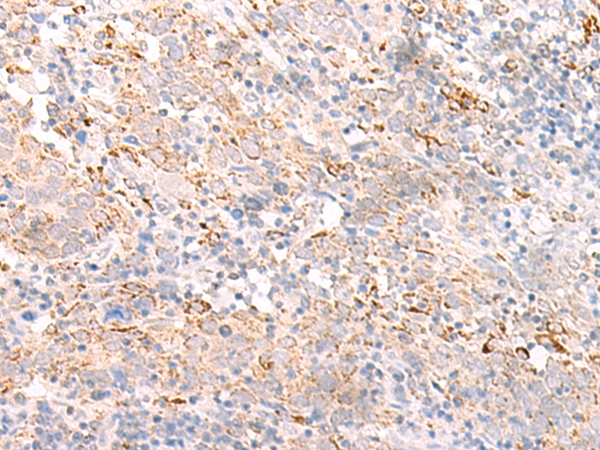

分类: 科研抗体货号: P06460别名: AS; HLAB; B-4901应用: WB,IHC反应种属: Human